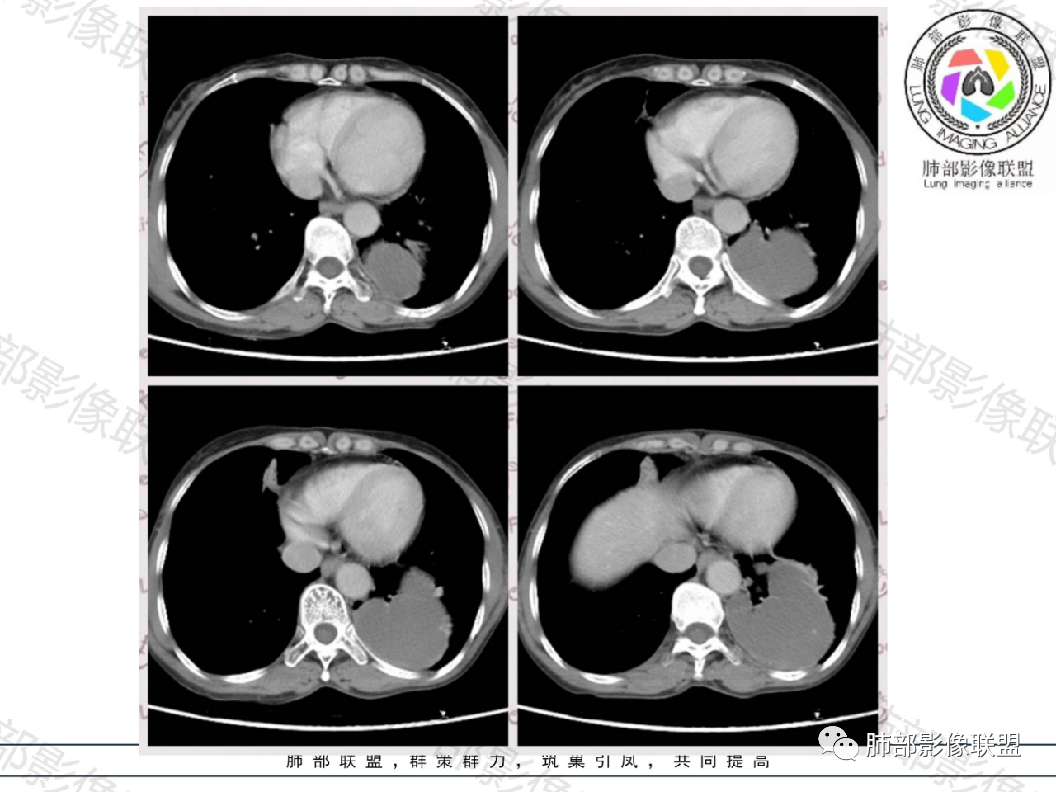

中年女性,体检发现左下肺占位,囊性为主,增强扫描大部分无强化,仅有局部边缘强化,似见内部分隔,可能为支气管壁,边缘有散在小结节,强化一致。

老年女性,查体发现,无症状,左肺下叶大肿块周围有同样小病灶,密度低,有包膜,多发囊样,内部无明显强化,周围轻度强化,支气管推移有狭窄,周围肺组织挤压,与胸膜宽基底相连,长轴与胸膜平行,考虑来源胸膜,SFT应该不均匀强化,考虑神经源性肿瘤,鞘瘤?鉴别SFT,肺隔离症,神经内分泌肿瘤等。

晨读:中年女性患者,无症状体检发现,胸部CT:左下肺外后基底段胸膜下不规则病灶,内部密度均匀,边缘部分光滑,部分分叶,呈膨胀性生长,增强扫描无强化,支气管血管显示不清,冠状位与脊柱的关系似D字征,综合考虑良性病变:

晨读:中年女性,无症状。胸部CT:左下肺后基底段肿块样病灶,边界清楚,患侧肺体积有减小。边缘光滑,囊性为主,可见分隔,相应肺段支气管未见,邻近肺受压,增强扫描强化不明显,仅有局部边缘强化,可能为支气管壁。个别层面似有肺外血管穿入。周围有散在小结节,形态、边缘、密度、强化一致。右下叶前基底段索条影。

中年女性,左下肺占位,以囊性为主,增强扫描大部分无强化,仅有局部边缘强化,内部似见分隔,边缘有散在小结节,强化一致;考虑良性病变,1.支气管囊肿?2.左肺下叶肺隔离症?3.隐球菌感染?4.右肺中叶内侧段慢性炎症。